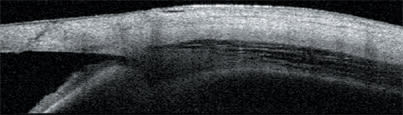

The Visante OCT is useful for determining if Descemet's-stripping endothelial keratoplasties are properly attached. This image also shows the inevitable meniscus-shaped cut and a relatively ragged trephine-induced edge.

Using the Visante OCT system to monitor Descemet's-stripping endothelial keratoplasties, surgeons have learned that the donor tissue typically continues to thin for approximately 3 months, affecting patients' vision. This image also shows the quantification of the donor tissue depth at various points.